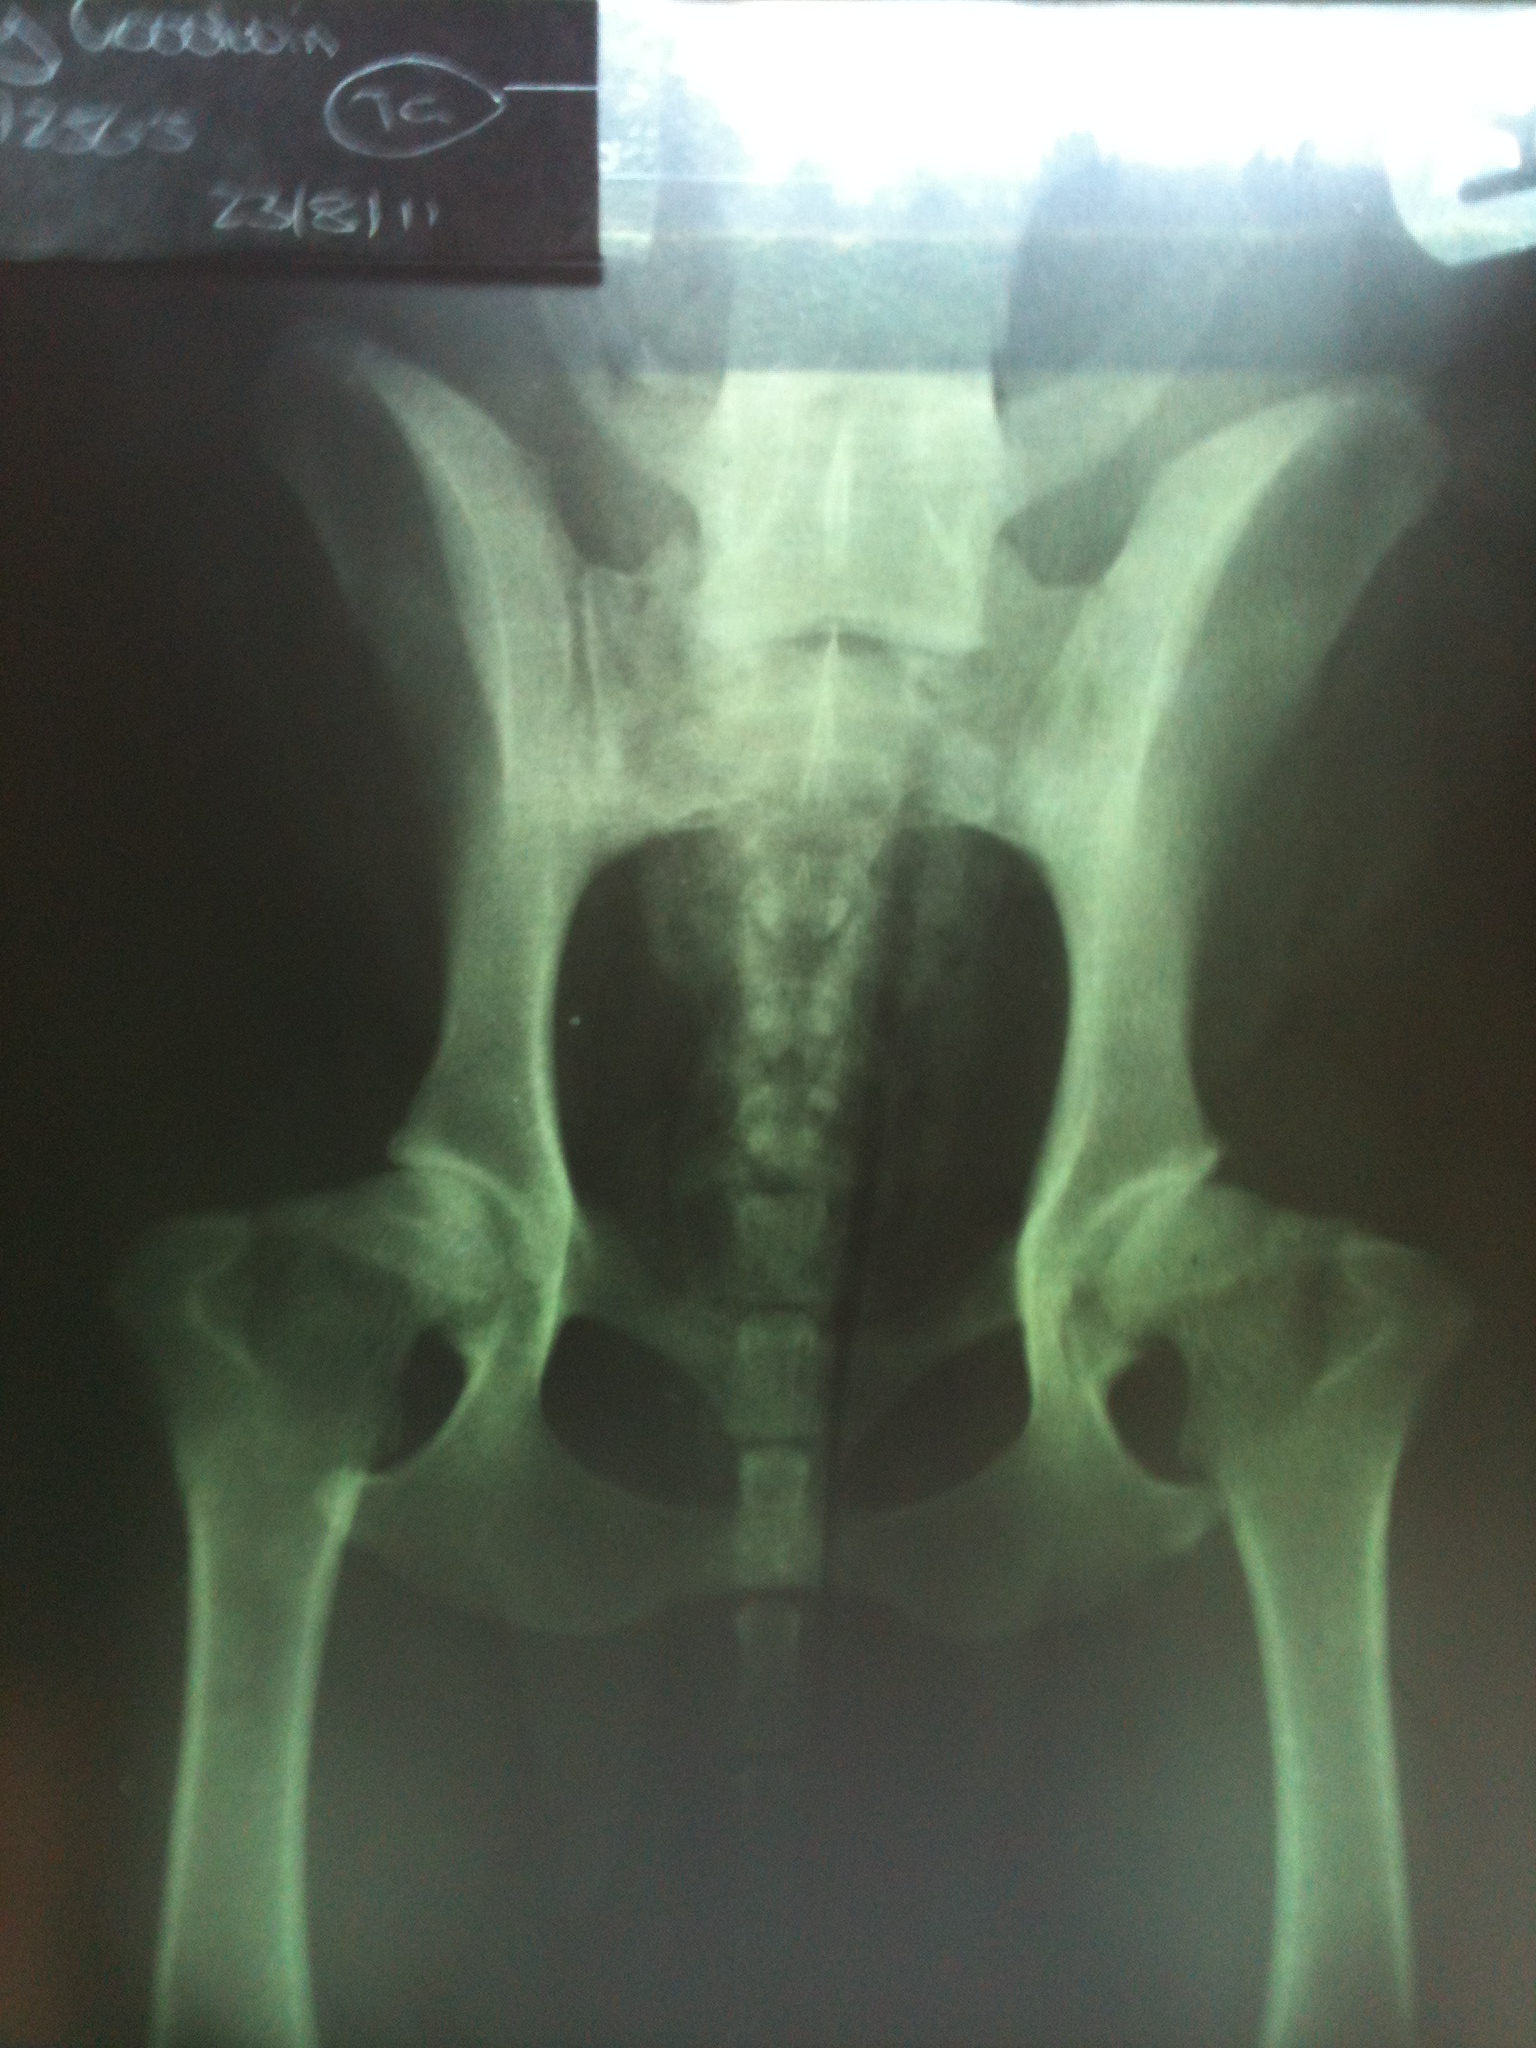

Tilly, our beloved hip-challenged diva, was on a mission to conquer her arthritis. The vet suggested swimming, and I was intrigued by the idea of hydrotherapy. So, I dove headfirst into research, I discovered where to study to become a canine hydrotherapist. I learned everything from canine anatomy to water management, and even how to handle post-surgery pups. I even took the plunge, sorry for the pun! And opened my own hydrotherapy centre, Haslington K9 Hydrotherapy was born, where Tilly became a regular swimmer. She was a natural, paddling away like a pro. It also ment I got to meet other breeds to including a dog de Bordeaux and a terrier, little to large, some dogs are not naturally drawn to swim so patience is key. Tilly was starting to show progress with her hips, when one day she started limping and not weight baring on her hind leg, a vet visit was in order, where it was revealed that she had a partial cruciate tear,. Surgery was unavoidable, but it was a success! Tiled then had to endured a few weeks of cage rest, after her final check up with the vets we were able to continue with her hydrotherapy, which she was happy about, and she was back to her old self in no time, until one fateful bank holiday weekend when her crucuate ligament snapped completely. No surgery this time, just more cage rest. Meanwhile, Poppy was putting on a show, limping around the kitchen for sympathy-what a drama queen! (Tilly’s X-ray below showing bilateral hip dysplasia )